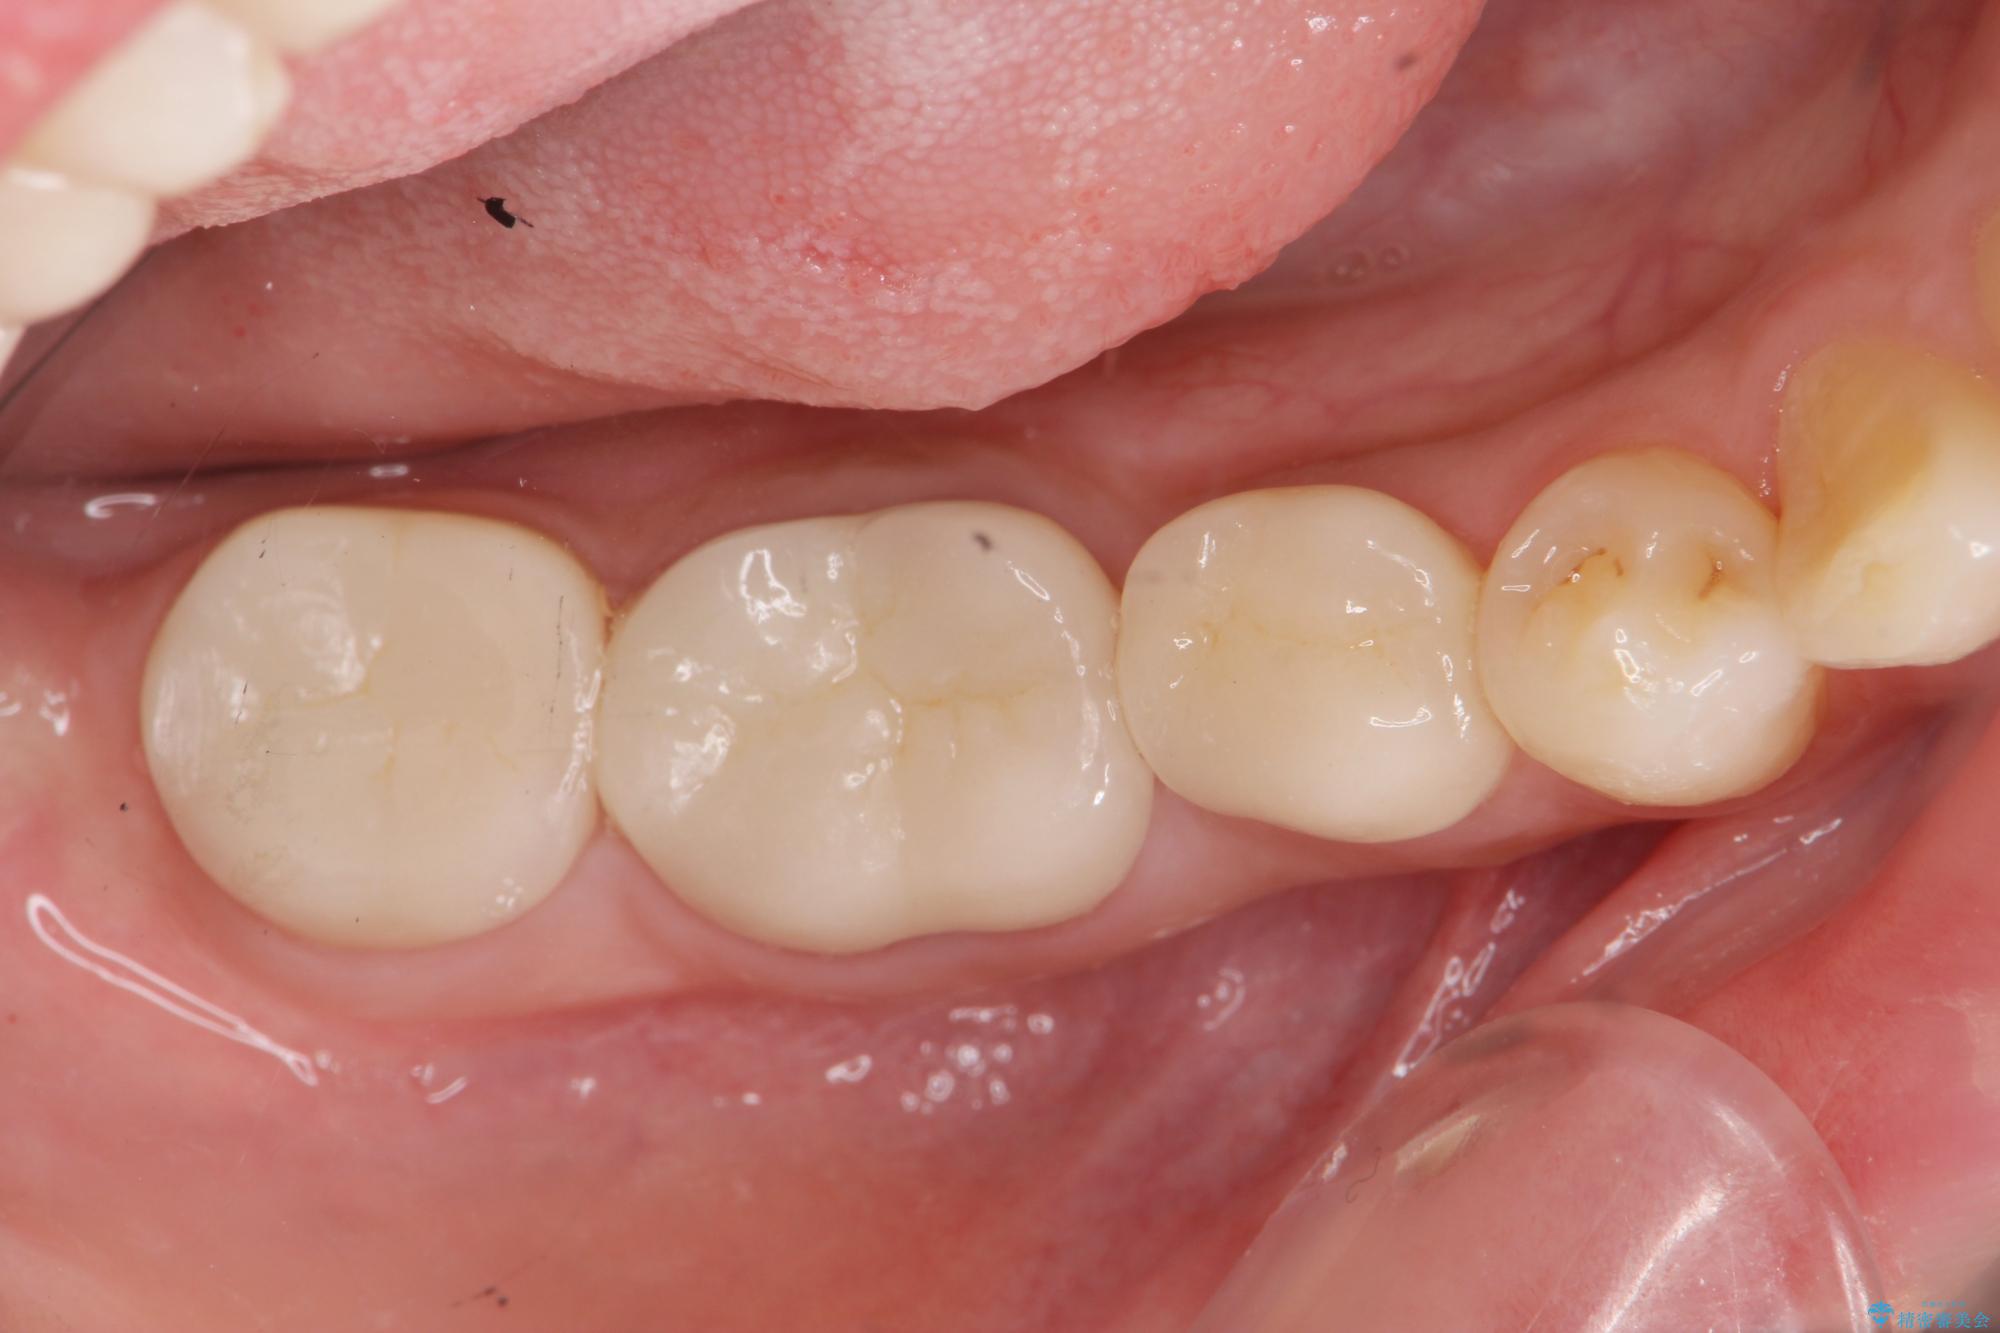

奥歯は既に根管治療が為されクラウンを装着する必要性がある状態ですが、歯の高さが低くクラウンの安定性・強度を担保するために歯周外科を行う治療計画としました。

歯周外科を行うことで、歯ぐきの位置を下げ歯の高さを作り出し安定したクラウンの装着が可能となります。また同時に舌の邪魔となっていた骨隆起の除去を行うこととしました。

- 37.4万円(ジルコニアクラウン×2・仮歯×2・歯周外科手術)費用は治療当時の料金となります